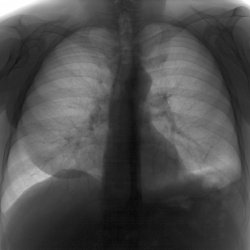

Мужчина 40 лет. Диагностическая  флюорография. Пришел на контроль, был поставлен диагноз 01.11.25 пневмония с\д, справа, в другой клинике. Смущает тень, которая видна только на задней проекции,...